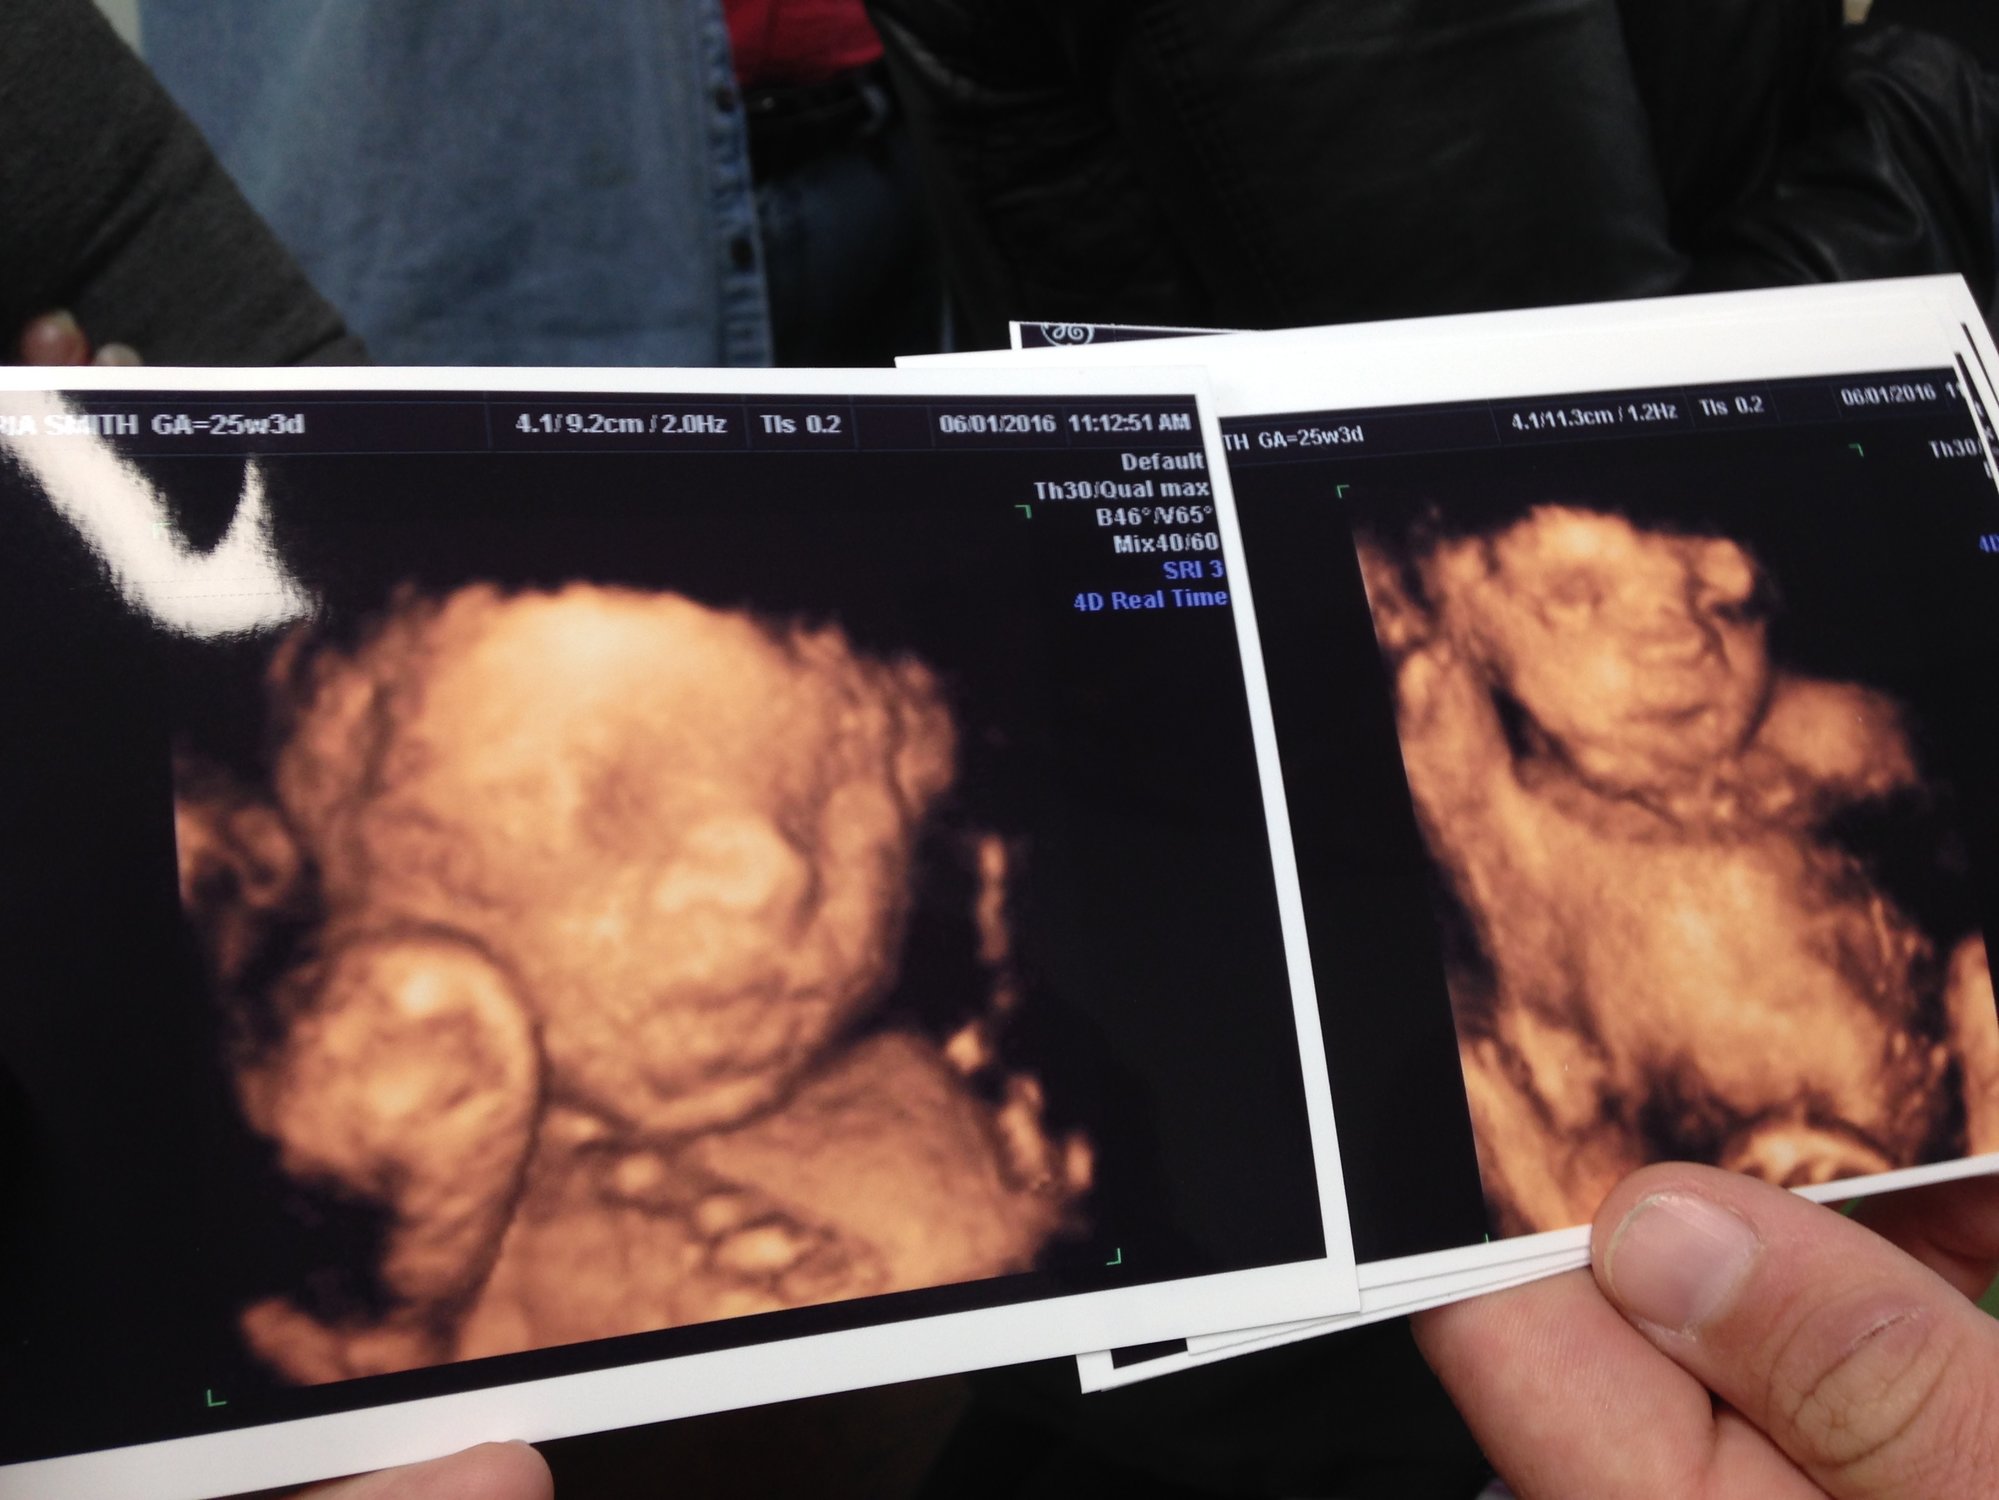

Sorry if giant. 3D ultrasounds are a bit weird but it was so cool to see his face. He has my lips for sure and his daddy's nose. Taken at 25w3d

she looks so content, almost like she's smiling